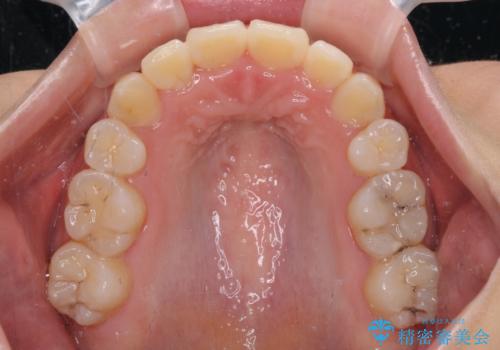

- 八重歯を気にして来院された患者様です。

上下ともに前突感と叢生が認められ、上顎の正中が著しく右側にずれていたため、上下左右第一小臼歯4本を抜歯し、ワイヤー矯正にて治療を行うこととしました。

移動量が多かったため、治療期間は通常より半年~1年ほど長くかかりましたが、上下の正中をほぼ同じ位置にまで移動させることができました。